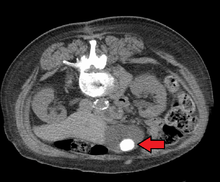

Images of a CT of gallstones

Mixed ("Brown Pigment") stones typically contain 20–80% cholesterol (or 30–70%, according to the Japanese- classification system).[30] Other common constituents are calcium carbonate, palmitate phosphate, bilirubin and other bile pigments (calcium bilirubinate, calcium palmitate and calcium stearate). Because of their calcium content, they are often radiographically visible. They typically arise secondary to infection of the biliary tract which results in the release of β-glucuronidase (by injured hepatocytes and bacteria) which hydrolyzes bilirubin glucuronides and increases the amount of unconjugated bilirubin in bile. Between 4% and 20% of stones are mixed.[3]